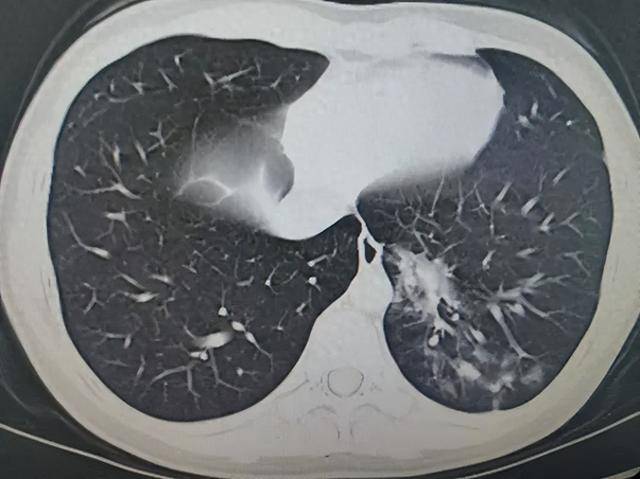

感染科副主任医师俞立飞接诊后,详细询问病史,发现昊昊肺部有啰音,综合评估,孩子更像是肺炎支原体,而后肺部CT的结果也证实了俞立飞的判断:左肺多发磨玻璃影,好像飘了一片“小云朵”,病原学检测结果提示:肺炎支原体感染。

杭州市第一人民医院供图